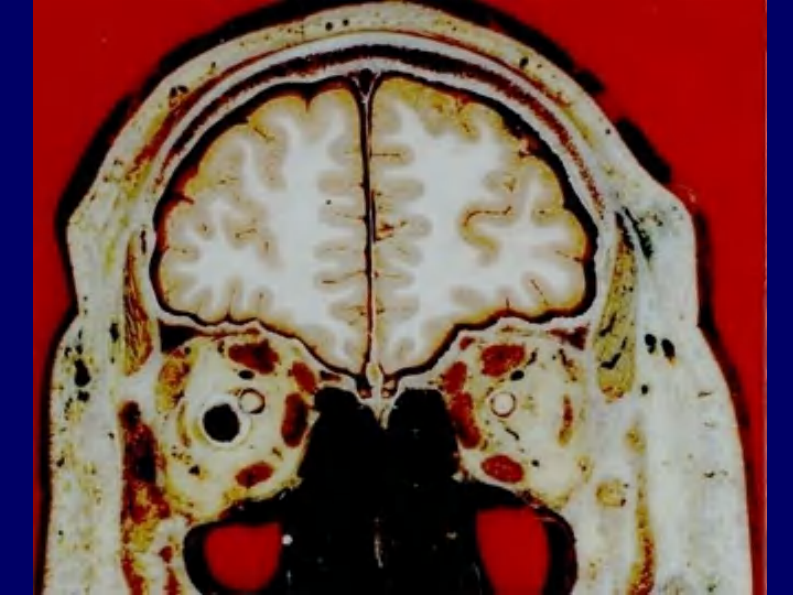

04 头部连续冠状断层解剖及MRI.pdf